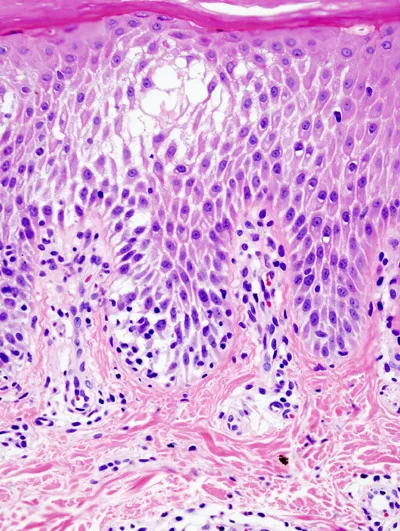

Cutaneous Histopathology Indian Medical PG Question 7: The skin biopsy shown below is most consistent with which of the following conditions?

- A. Lichen planus (Correct Answer)

Cutaneous Histopathology Explanation: ***Lichen planus***

- The image shows **basal cell degeneration** (liquefaction degeneration), a **sawtooth rete ridge pattern**, and a band-like inflammatory infiltrate primarily composed of lymphocytes at the dermo-epidermal junction, which are classic histological features of **lichen planus**.

- **Civatte bodies** (apoptotic keratinocytes forming colloid bodies) are typically present, resulting from keratinocyte damage at the basal layer.

- These features make lichen planus the most consistent diagnosis.

*Lichen nitidus*

- Characterized by **"ball and claw" lesions**, which are small, localized epidermal invaginations enclosing a central infiltrate of lymphocytes and histiocytes.

- The granulomatous infiltrate is more focal and circumscribed compared to the band-like pattern of lichen planus.

- While both are interface dermatitides, the architectural pattern differs significantly.

*Morphea*

- This is a localized form of **scleroderma**, characterized by increased **collagen deposition**, thickening of the dermis, and loss of adnexal structures like hair follicles and sweat glands.

- The inflammatory infiltrate is typically perivascular and interstitial, not band-like at the dermo-epidermal junction.

- The image does not show features of dermal fibrosis or homogenization of collagen bundles expected in morphea.

*Lupus erythematosus*

- Also shows **interface dermatitis** with basal vacuolar changes and lymphocytic infiltrate.

- However, lupus typically shows a **perivascular and periappendageal pattern** of infiltrate rather than the dense band-like pattern of lichen planus.

- Additional features in lupus include dermal mucin deposition, thickened basement membrane (PAS-positive), and follicular plugging.

- The dense, continuous band-like infiltrate and sawtooth rete ridges favor lichen planus over lupus.